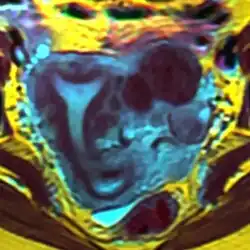

Arcuate uterus with fibroids seen on MRI

Helpful techniques to investigate the uterine structure are transvaginal ultrasonography and sonohysterography, hysterosalpingography, MRI, and hysteroscopy. More recently 3-D ultrasonography has been advocated as an excellent non-invasive method to delineate the condition.[5]